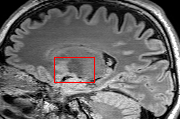

To test the impact of the iterative refinement on YODA’s translation quality, we compared regression and diffusion sampling on the RS data and present additional generation examples in Fig. 6. We observe that diffusion sampling visually resembles the appearance of the acquired images. Regression sampling preserves key anatomical features – the GM/WM boundary, WMHs (Fig. 4), the outline of the pallidum (Fig. 6) – but omits many high-frequency features. To investigate whether iterative refinement during diffusion sampling adds relevant and systematic medical information or only imitates acquisition noise, we performed ExpA sampling, i.e. averaging the output of several ( or ) diffusion trajectories. We observed a gradual loss of high-frequency details when increasing the (see also the supplementary video), indicating that the effect of the iterative refinement is non-systematic. For , the images are visually almost indistinguishable from the initial regression solution (see the supplementary video, and Fig.4 and 6). We directly compared the synthesis results of ExpA () and regression sampling quantitatively and found the differences to be minimal (SSIM: 99.73%, PSNR: 45.30 dB), i.e. diffusion sampling approaches the initial regression solution for a high . The quantitative analysis of the image quality (Tab. 1) showed that diffusion sampling impairs the assessed SSIM and PSNR in comparison to regression sampling for both the in- and external test sets, which we attribute to noise generation (Sec. 3.1). In turn, ExpA averages improved both metrics and, for , performed mostly on par with the regression solution in both test sets in terms of SSIM, while the PSNR in the RS was slightly increased (Tab. 1). However, we observed that ExpA sampling YODA improves the replication of systematic 3D low-frequency image intensity drifts (bias fields) due to the 3D synchronization in 2.5D diffusion sampling. Yet, this apparent advantage did not generalize to the external MBB dataset, as bias fields are MR protocol-specific.

To assess the suitability of YODA-generated images for WMH detection independent of segmentation tools, we also calculated the CNR (15) of WMHs. This confirmed that the contrast of WMHs is preserved in the regression images, whereas we noted slightly reduced WMH contrast for diffusion and ExpA-sampled images (Tab. 1).

However, we observed some missing small WMHs (third row, Fig. 9) in the synthetic FLAIR images. Due to the weak input signal, translating small WMHs in inherently difficult and, thus, omitting these WMHs can be seen as conservative. In contrast, a more speculative translation bears the risk of false-positive, hallucinated WMHs (compare e.g., SynDiff, Fig. 4).

In Brats, we observed one case with FLAIR hyper- rather than hypo-intense tumor cavity (Fig. 9, fifth row).

While this constitutes a semantic error suggesting soft-tissue rather than fluids, we note that the differentiation from T1w and T2w images alone is ambiguous.